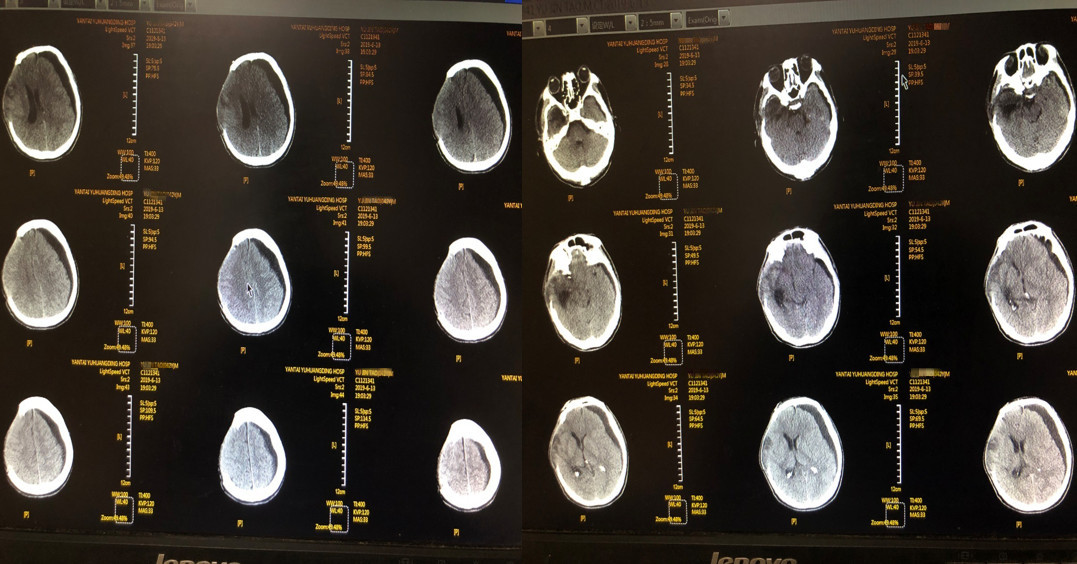

男性,43岁,因“高处坠落致头部外伤伴意识障碍8小时”于2019年5月12 日21:30入院。

神志昏迷状,GCS评分:E1V1M4。

右额可见大片皮肤擦伤,伴形状不规则伤口长约8cm(已缝合)。

右眼睑青紫肿胀,右侧瞳孔直径6mm,光反射消失,左侧瞳孔直径3mm,光反射迟钝。双侧鼻腔流血。

1、患者受伤当时头颅CT以蛛网膜下腔出血为主要表现,结合病史,高度怀疑颅内动脉瘤破裂所致,遇到此类情况,要仔细分析病情因果关系;由于患者入院时伤情较重,手术不能拖延,没有时间进一步行CTA及DSA检查,给手术时探查责任动脉瘤造成困难。

1、急性颅脑创伤合并颅内动脉瘤破裂临床上较为少见,大多以急性颅脑创伤就诊,容易漏诊颅内动脉瘤破裂。任何一个颅脑创伤患者都必须祥细了解其受伤原因、过程,分析受伤机制,如果无明显外在因素促使头颅受伤,就要高度怀疑颅内或全身其他疾病导致患者跌倒或坠落从而使头颅受伤可能。既有可能颅内动脉瘤破裂后患者跌倒或坠落并发颅脑创伤,也有可能头颅受伤诱发颅内动脉瘤破裂。当CT影像显示的蛛网膜下腔出血广泛而且主要位于鞍上池、环池、侧裂池等颅底池或者蛛网膜下腔出血部位难以用颅脑创伤的受伤机制来解释时就要考虑急性颅脑创伤合并有颅内动脉瘤破裂可能。本例伤后外院头颅CT的情况正属此种情况,团队临床经验丰富,准确做出了判断。

3、从术前、术后CT影像来看,术者手术技能较强,术后在NICU施行了ICP监测、镇痛、镇静等神经重症规范化的管理和治疗,这是确保脑功能受损尽可能小,术后患者较快清醒,最终患者获得较好预后的基础。

1、颅脑创伤后的蛛网膜下腔出血(SAH)很多见,但如果CT提示以纵裂池出血、鞍上池不对称积血、外侧裂积血、或第四脑室出血为主要表现,结合受伤状况(头痛/昏迷可能先于外伤),要多一种思考:是否动脉瘤破裂出血、或者其他血管病发作,是创伤的真正始动因素。有怀疑则积极进行相应检查(如CTA等)来明确。本例术前已经脑疝,直接开颅血肿清除、颅内探查动脉瘤夹闭、去骨瓣减压,是“脑疝救治”这一主线、“动脉瘤探查夹闭”这一辅线救治的合理结合。术后有条件则需要及时再行血管检查。本例颅骨修补前DSA检查,既是动脉瘤夹闭效果的复查,也是全脑血管的完善检查。